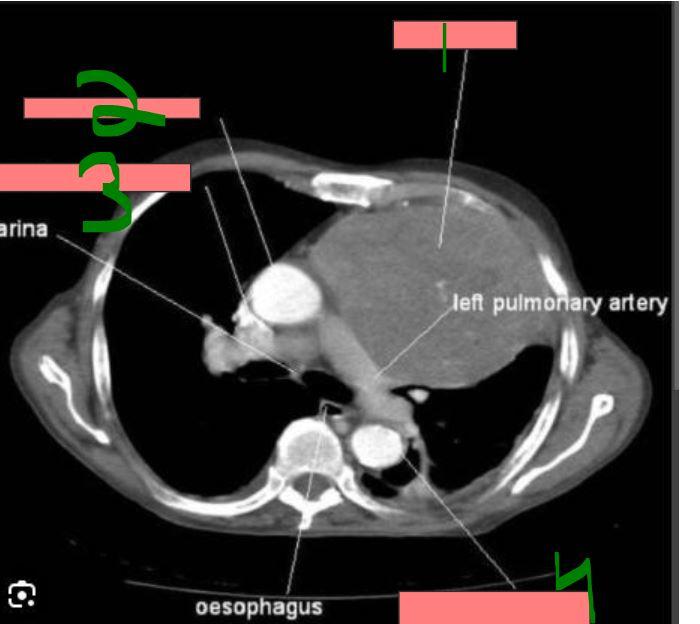

card image

What is 1?

thymoma

2?

ascending aorta

3?

superior vena cava

4?

descending aorta